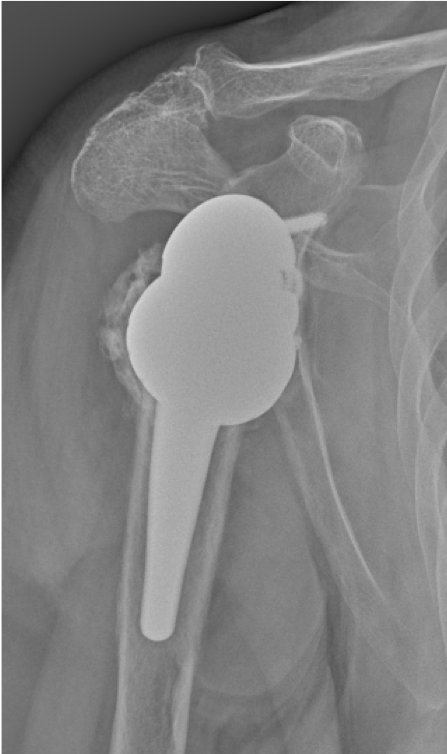

Post-op

Implantation of the LINK Embrace

- Short stem, uncemented

- Reverse Offset Tray for humerus lateralization

- Reverse Glenoid Baseplate with the TrabecuLink structure for bone integration with central and peripheral screws

- Neutral glenosphere 39 mm diameter

Result:

- Slight stem subsidence in first-follow-up

- Stabilized stem position in second follow-up

- Fracture consolidation

Clinic:

- Shoulder actively mobile

- 70° in elevation and abduction

- No pain